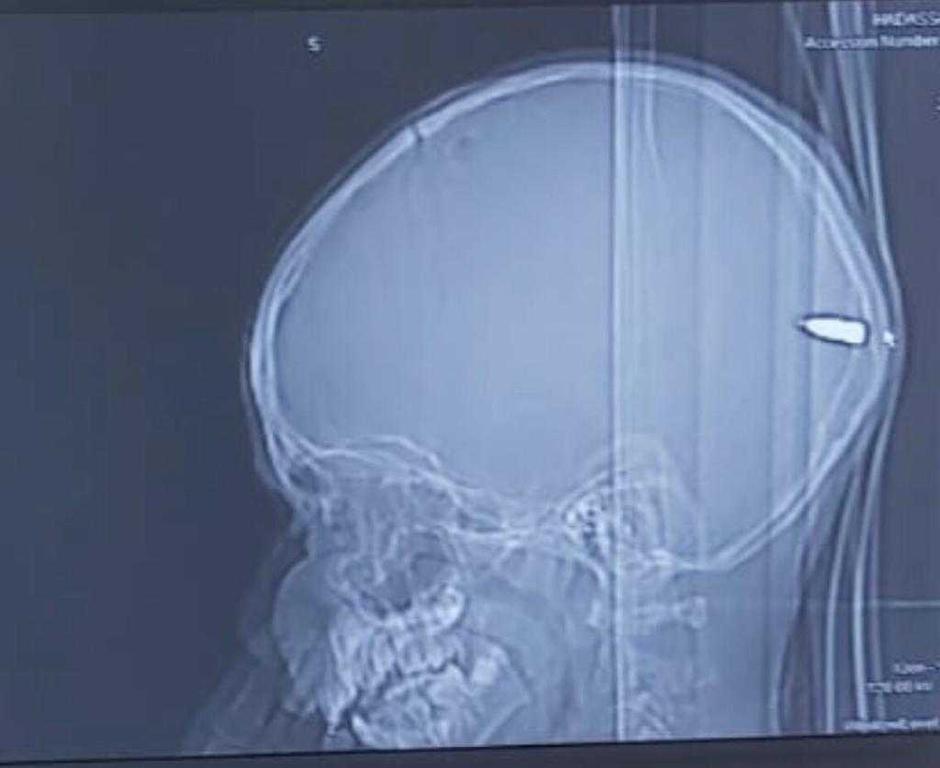

Neurokirurg Guy Elor odmah je zatražio CT glave nakon čega je u dječakovu mozgu otkrio metak

Liječnici su ga odmah pregledali, a na glavi su mu pronašli malenu ranu i krv na vlasištu. Odmah su mu napravili CT nakon čega su otkrili kako dječak ima metak u glavi.

Metak je prošao kroz lubanju i zaustavio se u dječakovu mozgu.

Foto: Hadassah University Hospital